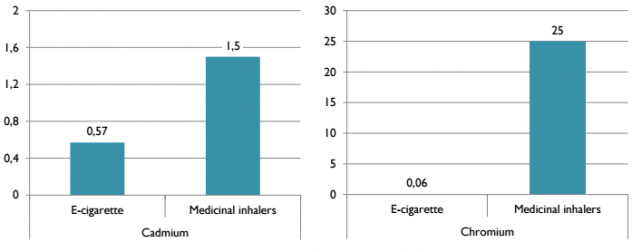

В следующей таблице сравнили содержание тяжелых металлов в электронных сигаретах (показатели во втором столбце) и в обычных (показатели в третьем столбце). Как можно заметить, в паре от электронных сигарет по многим позициям больше тяжелых металлов:

Однако эти значения довольно незначительны. Для сравнения, Доктор Фарсалинос сопоставил их содержание с разрешимым в медицине порогом для медицинских ингаляторов:

- Кадмий и хром